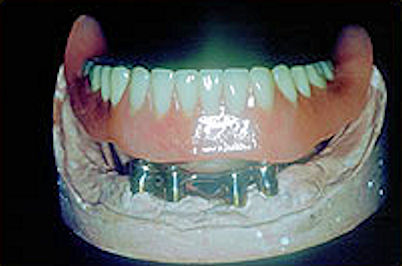

Inside the denture showing the attachments or clips

Once the metal bar and the denture framework have been fitted together properly, the teeth are temporarily placed on the framework in wax. The whole denture is then tried in your mouth. If you are satisfied with the try-in denture, we will complete it into the final product.

You will have to return for another visit to have the completed denture inserted. When the denture is inserted, the denture is clipped onto the bar or snapped onto the ball attachments.